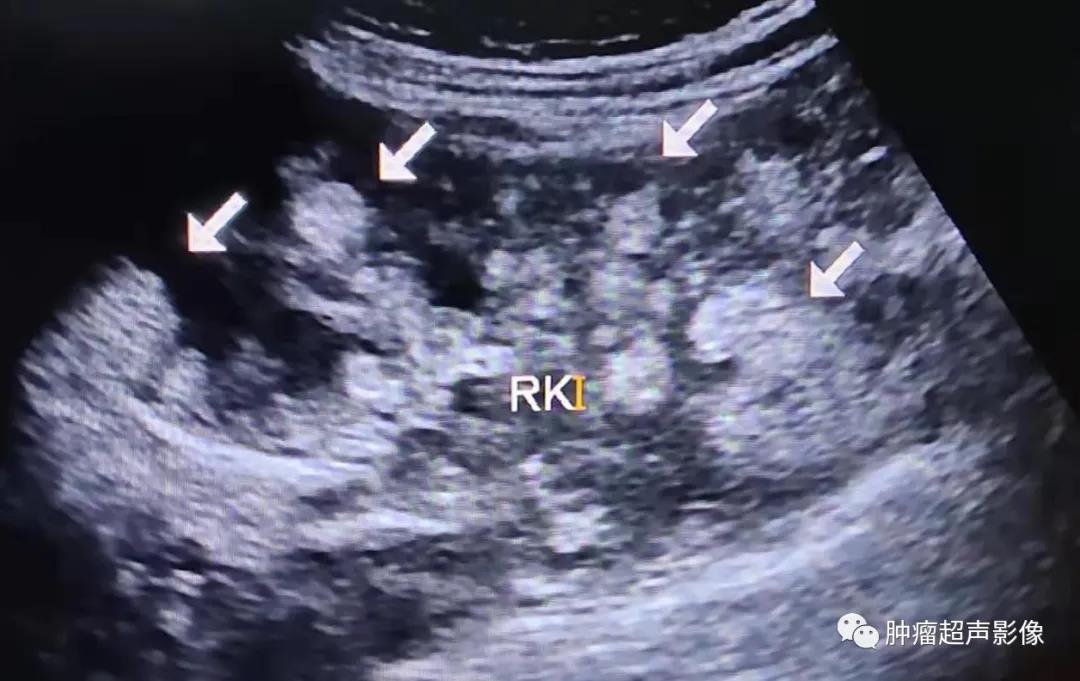

超声检查发现双肾多发AML,尤其是肿瘤数目较多、瘤体较大、肾脏轮廓不清时要想到TSC的可能,并询问相关病史,并观察面部、建议颅脑CT检查等。肾囊肿在TSC中也较常见,是该病临床诊断的次要指征。肝AML在超声上与血管瘤表现类似,均表现为大小不等圆形或椭圆形偏强回声团块,肝AML含有脂肪成分,回声比血管瘤回声更强一些,结合TSC病史,肝脏多发偏强回声占位应首先考虑为AML。

体检发现双肾多发错构瘤,双肾密集分布,考虑结节性硬化症表现,建议头颅检查(病例由江口县人民医院胡海英医师提供)

女,61,因肾肿瘤入院治疗,超声及CT示两肾多发错构瘤,建议头颅检查。